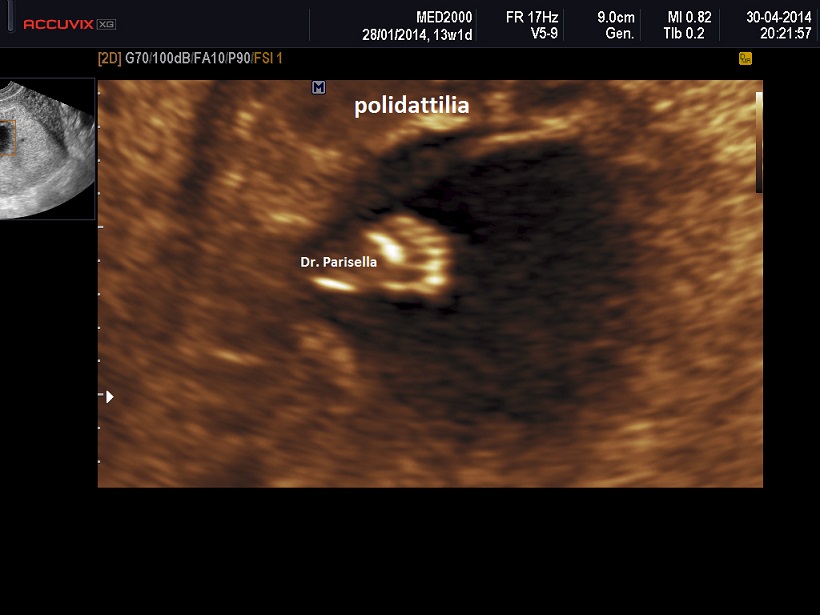

polidattilia

anomalie arti (fusione radio ulna, polidattilia )

L) anomalie arti (Limbs): aplasia radio, fusione radio ulna, polidattilia